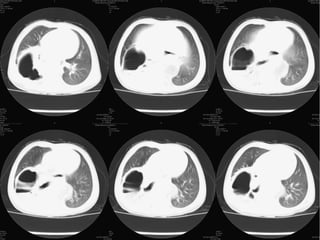

A 2-year-old girl who

presented with intermittent abdominal

pain and mild shortness

of breath caused by a small

Bochdalek hernia. a Chest radiograph

shows a moderate left

plural effusion and mild small

bowel dilatation. b Close-up

image of the splenic flexure of

the colon obtained during an

enema using water-soluble contrast

material shows a complete

obstruction of the colon with a

beak-like appearance. At surgery,

ischemic colon was found

in the left chest incarcerated by

a 7-mm Bochdalek hernia